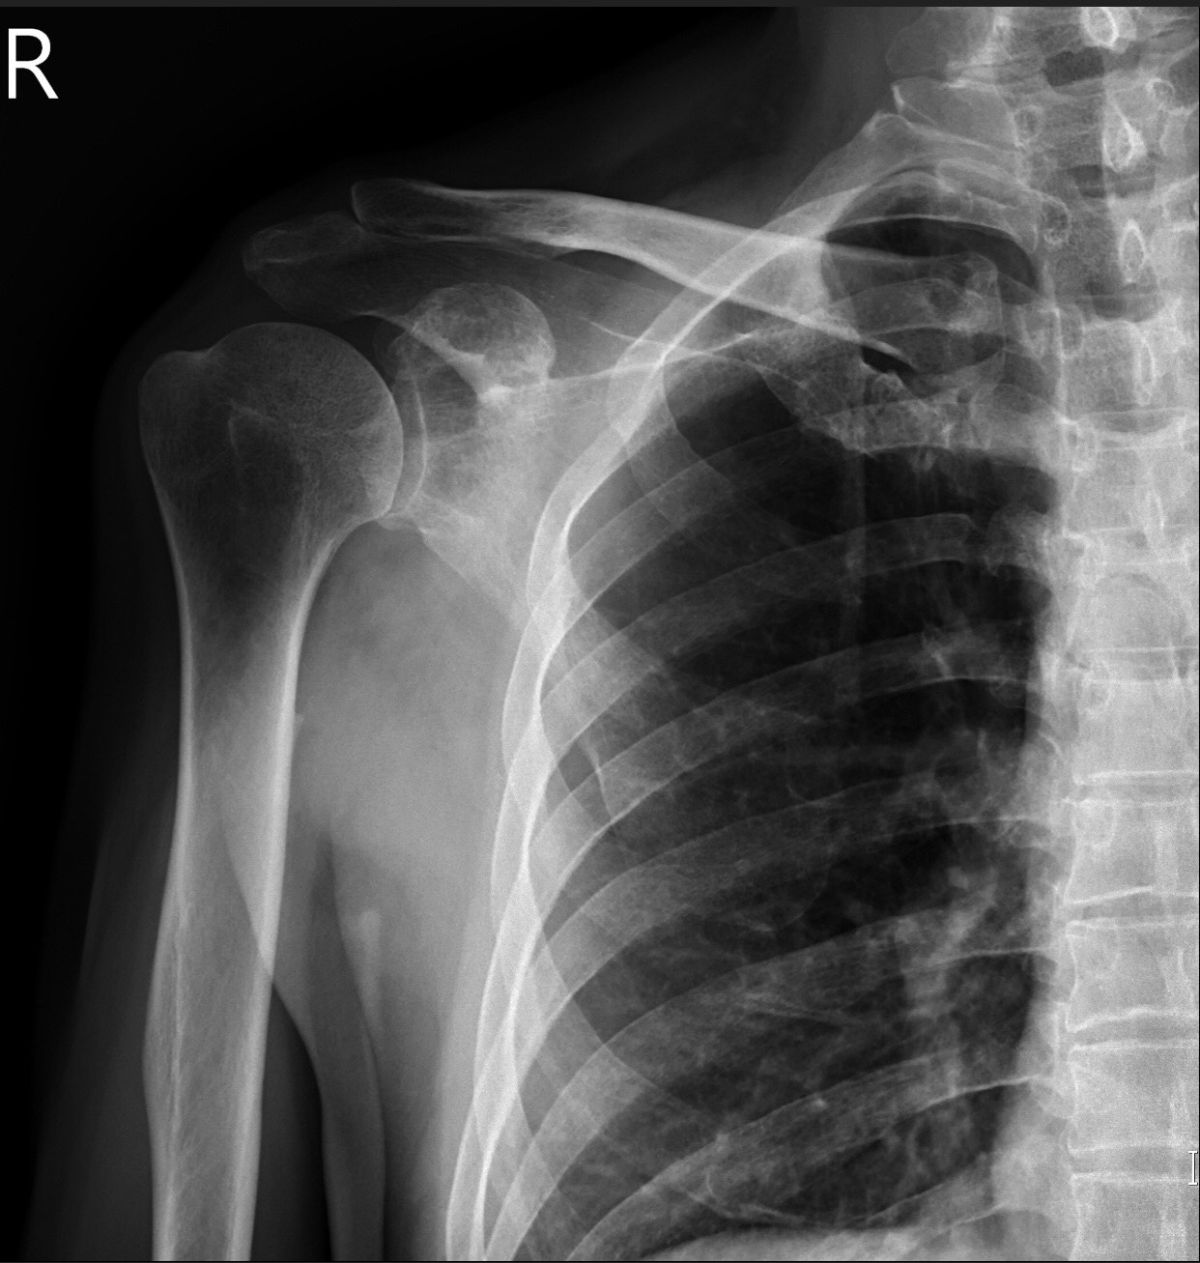

53歲的何先生右肩疼痛已有半年,工作結束特別容易痠痛,晚上睡覺痛得更厲害,常常要吃止痛藥才可以入睡。何先生到診所求診未見改善,後至安南醫院骨科求診許惟傑醫師,X光發現在肩胛骨有一溶骨性病變,懷疑是惡性腫瘤合併骨轉移;透過病理切片與胸部電腦斷層檢查,發現在前縱膈腔有一腫瘤病灶,大小約2.7公分,經過胸腔外科實施手術切除,證實是胸腺癌。

許惟傑說,胸腺癌好發年紀為中年,男性比較略高於女性,大多數病患有胸部不適、咳嗽、橫膈神經痲痺、上腔靜脈阻塞或遠處骨轉移引起的疼痛,遠端轉移好發位置為肋膜、肺部、骨頭及肝臟,依據醫療文獻,骨頭轉移大多發生於脊椎與長骨,像何先生轉移到肩胛骨的情況,全球只有零星個案報告。